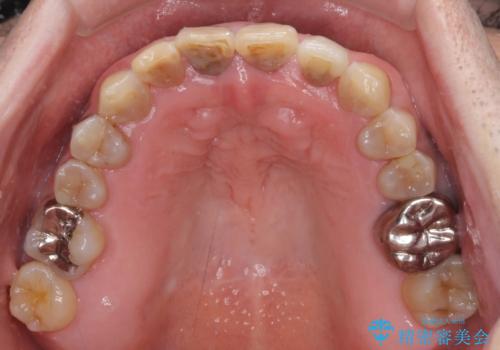

上顎の狭窄歯列 インビザラインによる拡大矯正

- 前歯の叢生と臼歯のクロスバイトを気にして来院された患者様です。

急速拡大装置による上顎の側方拡大を行い、その後はインビザラインより歯列を改善することとしました。

20代後半以降の男性は上顎骨の側方拡大処置の成功率が低く、今回も骨を拡大することができませんでした。

しかしながら、歯列を側方に拡大することができ、その後はインビザラインにて叢生を解消することができました。